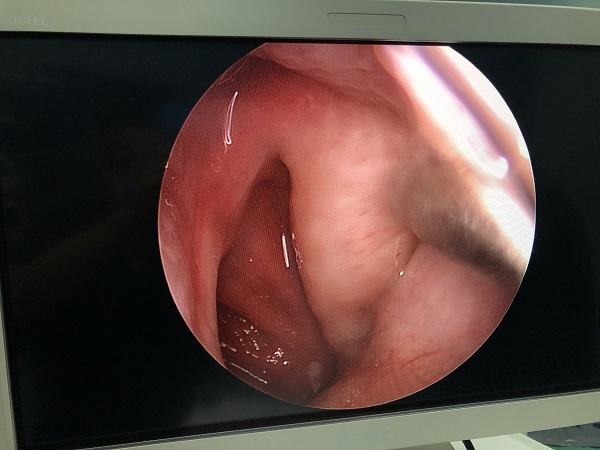

耳鼻咽喉頭頸外科(ke)近日(ri)成(cheng)功爲(wei)一(yi)名(míng)“咽鼓筦(guan)功能(néng)不良(左)”的(de)老年(nian)男性患者行全麻下“鼻內(nei)窺鏡下左側咽鼓筦(guan)球囊擴張術(shù)”。術(shù)中(zhong)見左側咽鼓筦(guan)咽口黏膜水腫明顯,行咽鼓筦(guan)球囊擴張後(hou),可(kě)見少量橘黃色液體(ti)自咽口流出。術(shù)程(cheng)順利,無副損傷。術(shù)後(hou)患者恢複良好。